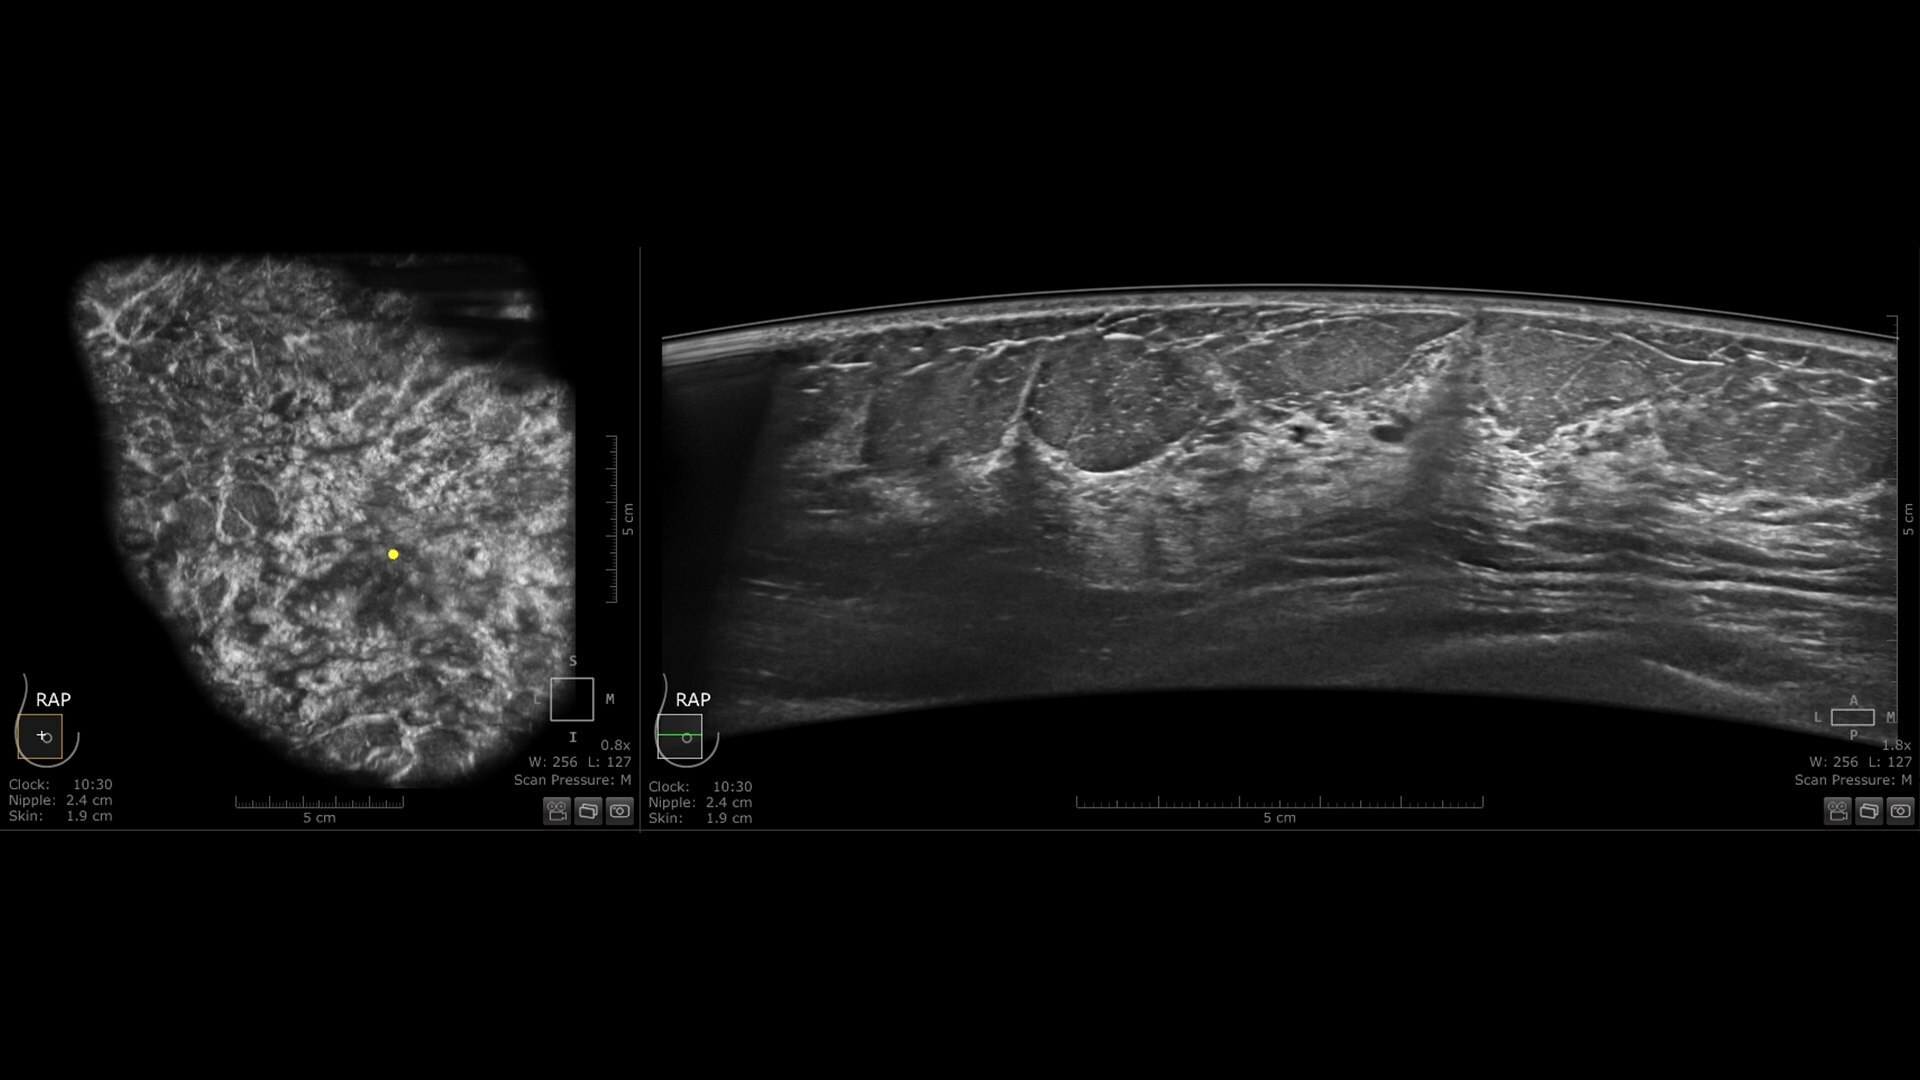

Excellent image quality and 40% faster scan speed

cSound Imageformer, software-based processing, produces exquisite, reproducible images by leveraging automatic focus at every pixel.

Fast Scan increases scan speed by 40%*, fostering improved efficiency and patient throughput.

s-curve-csound-desktop-st-en